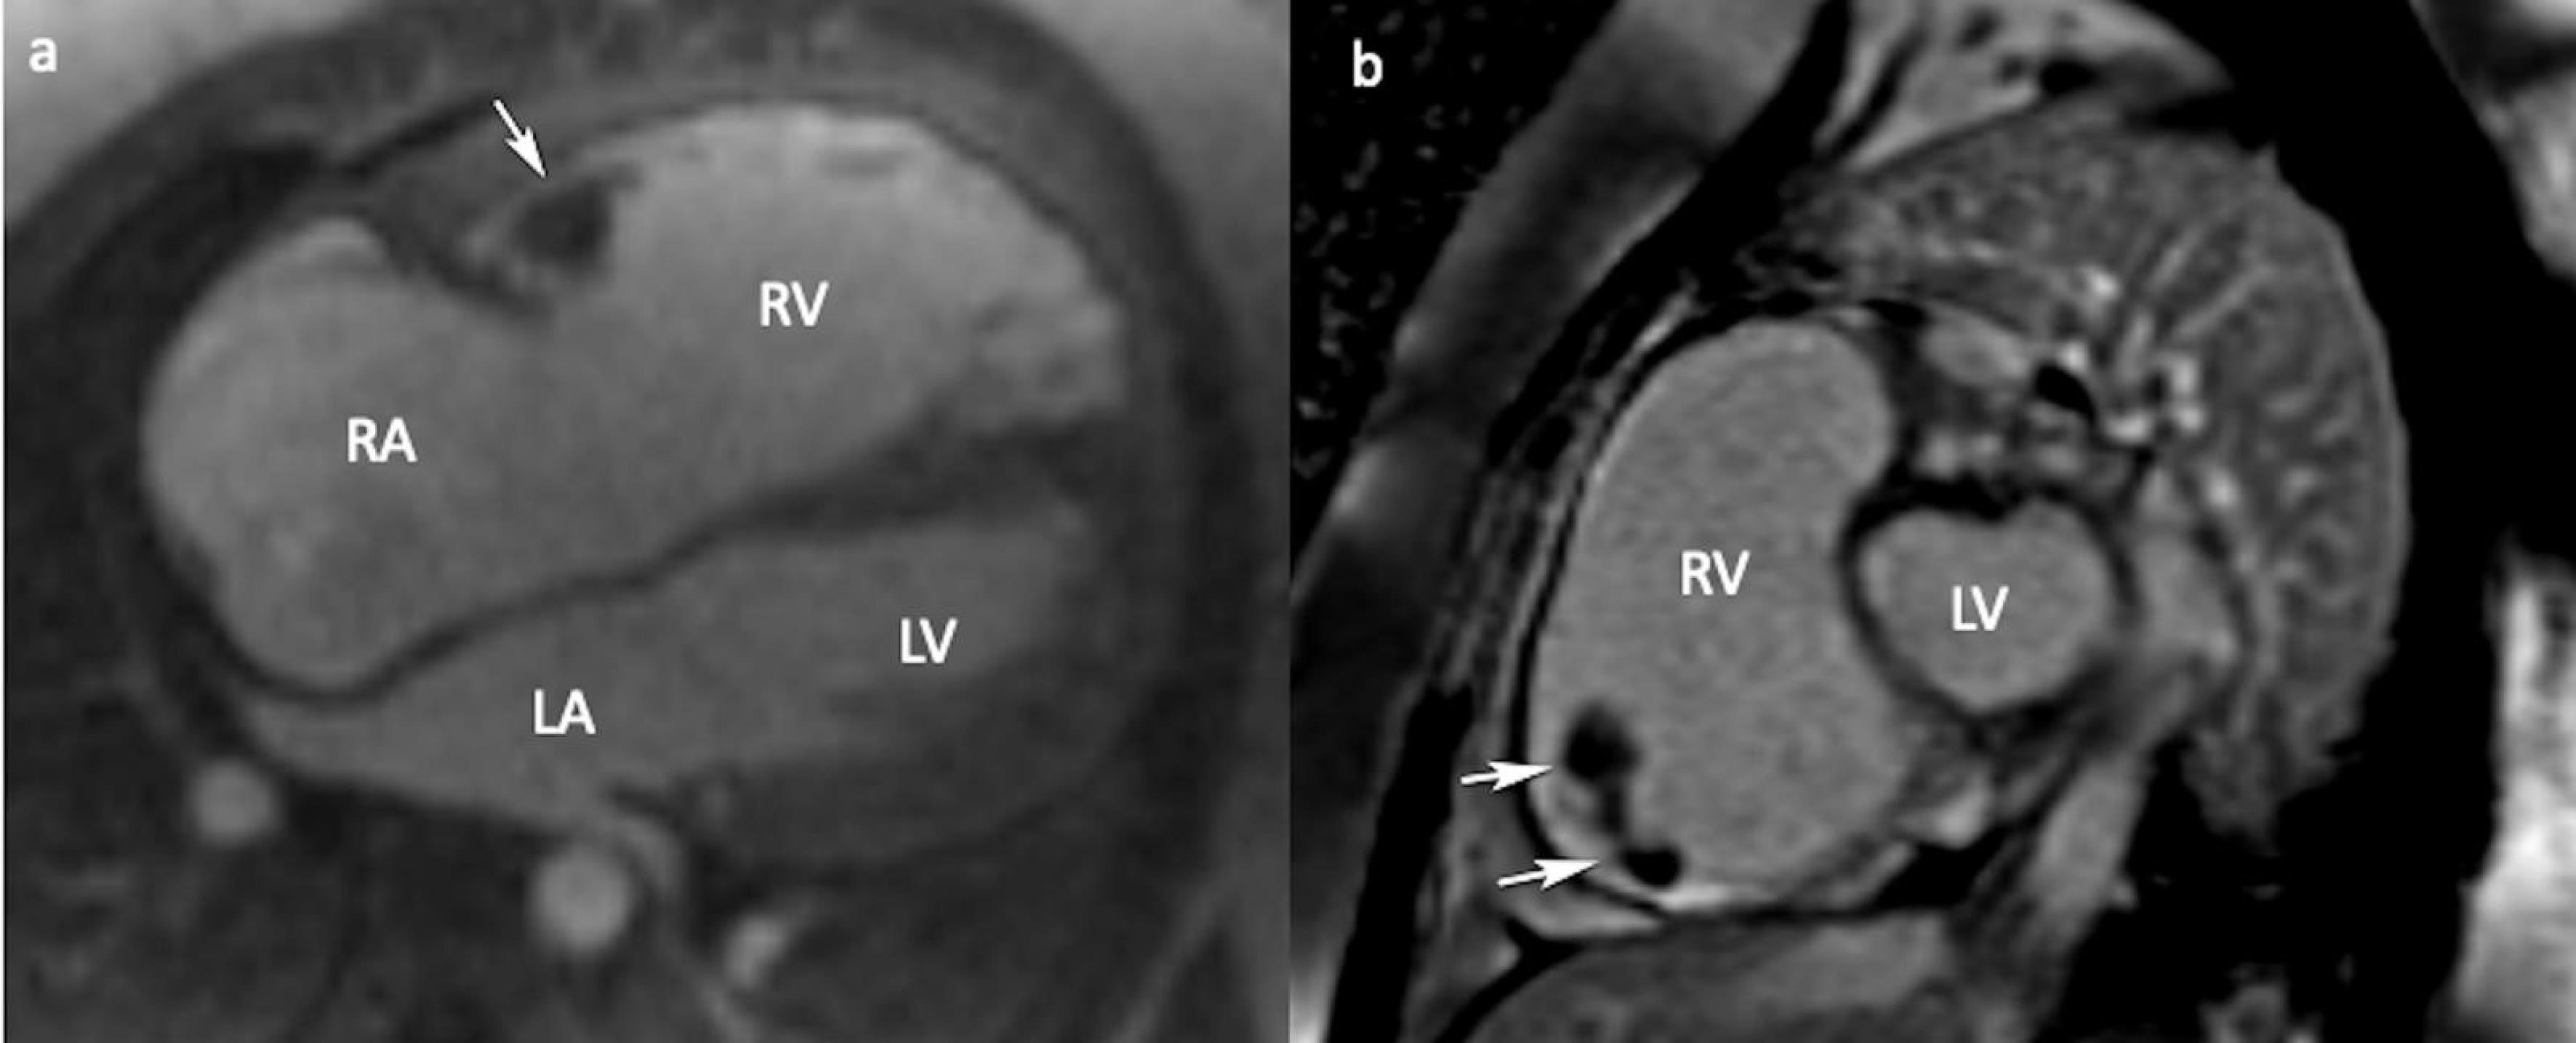

Figure 4.

CMR 4-chamber (a) and short-axis (b) LGE views showing non contrast enhancing thrombus (arrows). (CMR: Cardiac magnetic resonance, LGE: Late gadolinium enhancement, RA: Right atrium, LA: Left atrium, RV: Right ventricle, LV: Left ventricle)

A 24-year-old female patient was admitted to our tertiary center with chest pain. She had no family history of cardiac disease or sudden cardiac death. Her electrocardiogram (ECG) was sinus rhythm and T wave negativity was detected in leads V1-5. (Figure 1) TTE showed a slight decrease in LV ejection fraction as 45%, prominently dilated right heart chambers, decreased RV functions (TAPSE: 11, tricuspid annular peak systolic velocity: 7.7), severe tricuspid regurgitation (Supplementary file 1, Video 1). Additionally, an image of 13.6 x 9.3 mm, hyperechoic, consistent with thrombus was observed in the lateral wall of the RV (Figure 2). No thromboembolism was reported in the pulmonary CTA. The patient underwent cardiac magnetic resonance imaging (CMR) for morphological and functional assessment of the heart. The CMR images showed enlarged RV and right atrium, severe hypokinesia of the RV, dyskinesia in the free wall of RV and paradoxical movement in interventricular septum, and wall irregularity in both ventricles (Figure 3). In the cardiac MRI, The LV ejection fraction was 49%, the LV end-systolic volume was 143 mL, end-diastolic volume was 73 mL, and stroke output was 60 mL. The LV end-diastolic volume index (LVEDVI) was 74 mL/m2, the LV end-systolic volume index (LVESVI) was 42 mL/m2. The RV ejection fraction was 20%, the RV end-systolic volume was 430 mL, end-diastolic volume was 343 mL, and stroke output was 87 mL. The RV end-diastolic volume index (RVEDVI) was 221 mL/m2, the RV end-systolic volume index (RVESVI) was 176 mL/m2. The late gadolinium images depicted diffuse enhancement in the right ventricular free wall and inferior wall. The left ventricular inferior septum showed midwall enhancement. A nodular mass was noted on the lateral wall of RV in the vicinity of the tricuspid valve which did not uptake gadolinium and was compatible with thrombus (Figure 4). As a result of these findings, genetic analysis was performed with a high suspicion of arrhythmogenic cardiomyopathy. The genetic analysis revealed a homozygous nonsense mutation in the desmoglein-2 gene, proven to be pathogenic in databases, and the diagnosis of arrhythmogenic cardiomyopathy was definitively confirmed with the findings from TTE, ECG, CMR, and genetic tests, which are part of the aforementioned Padua criteria.